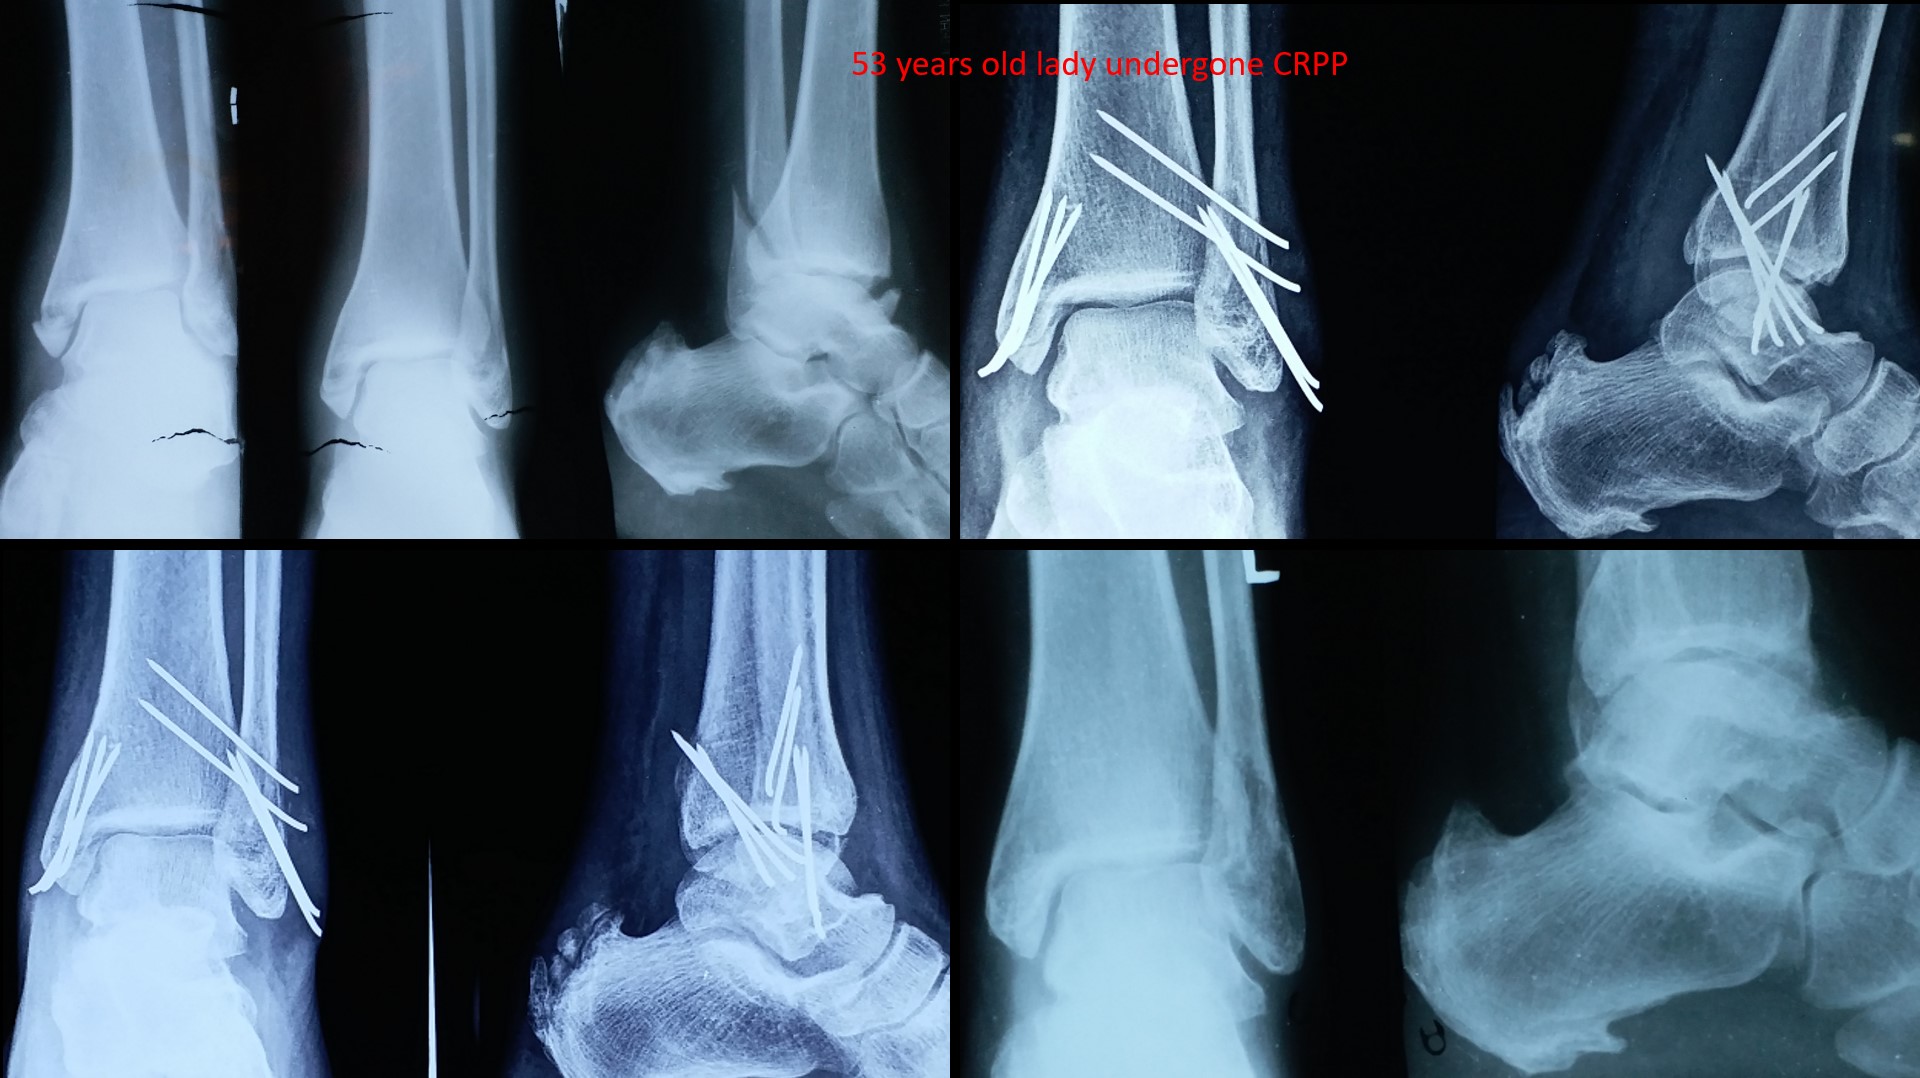

ANKLE